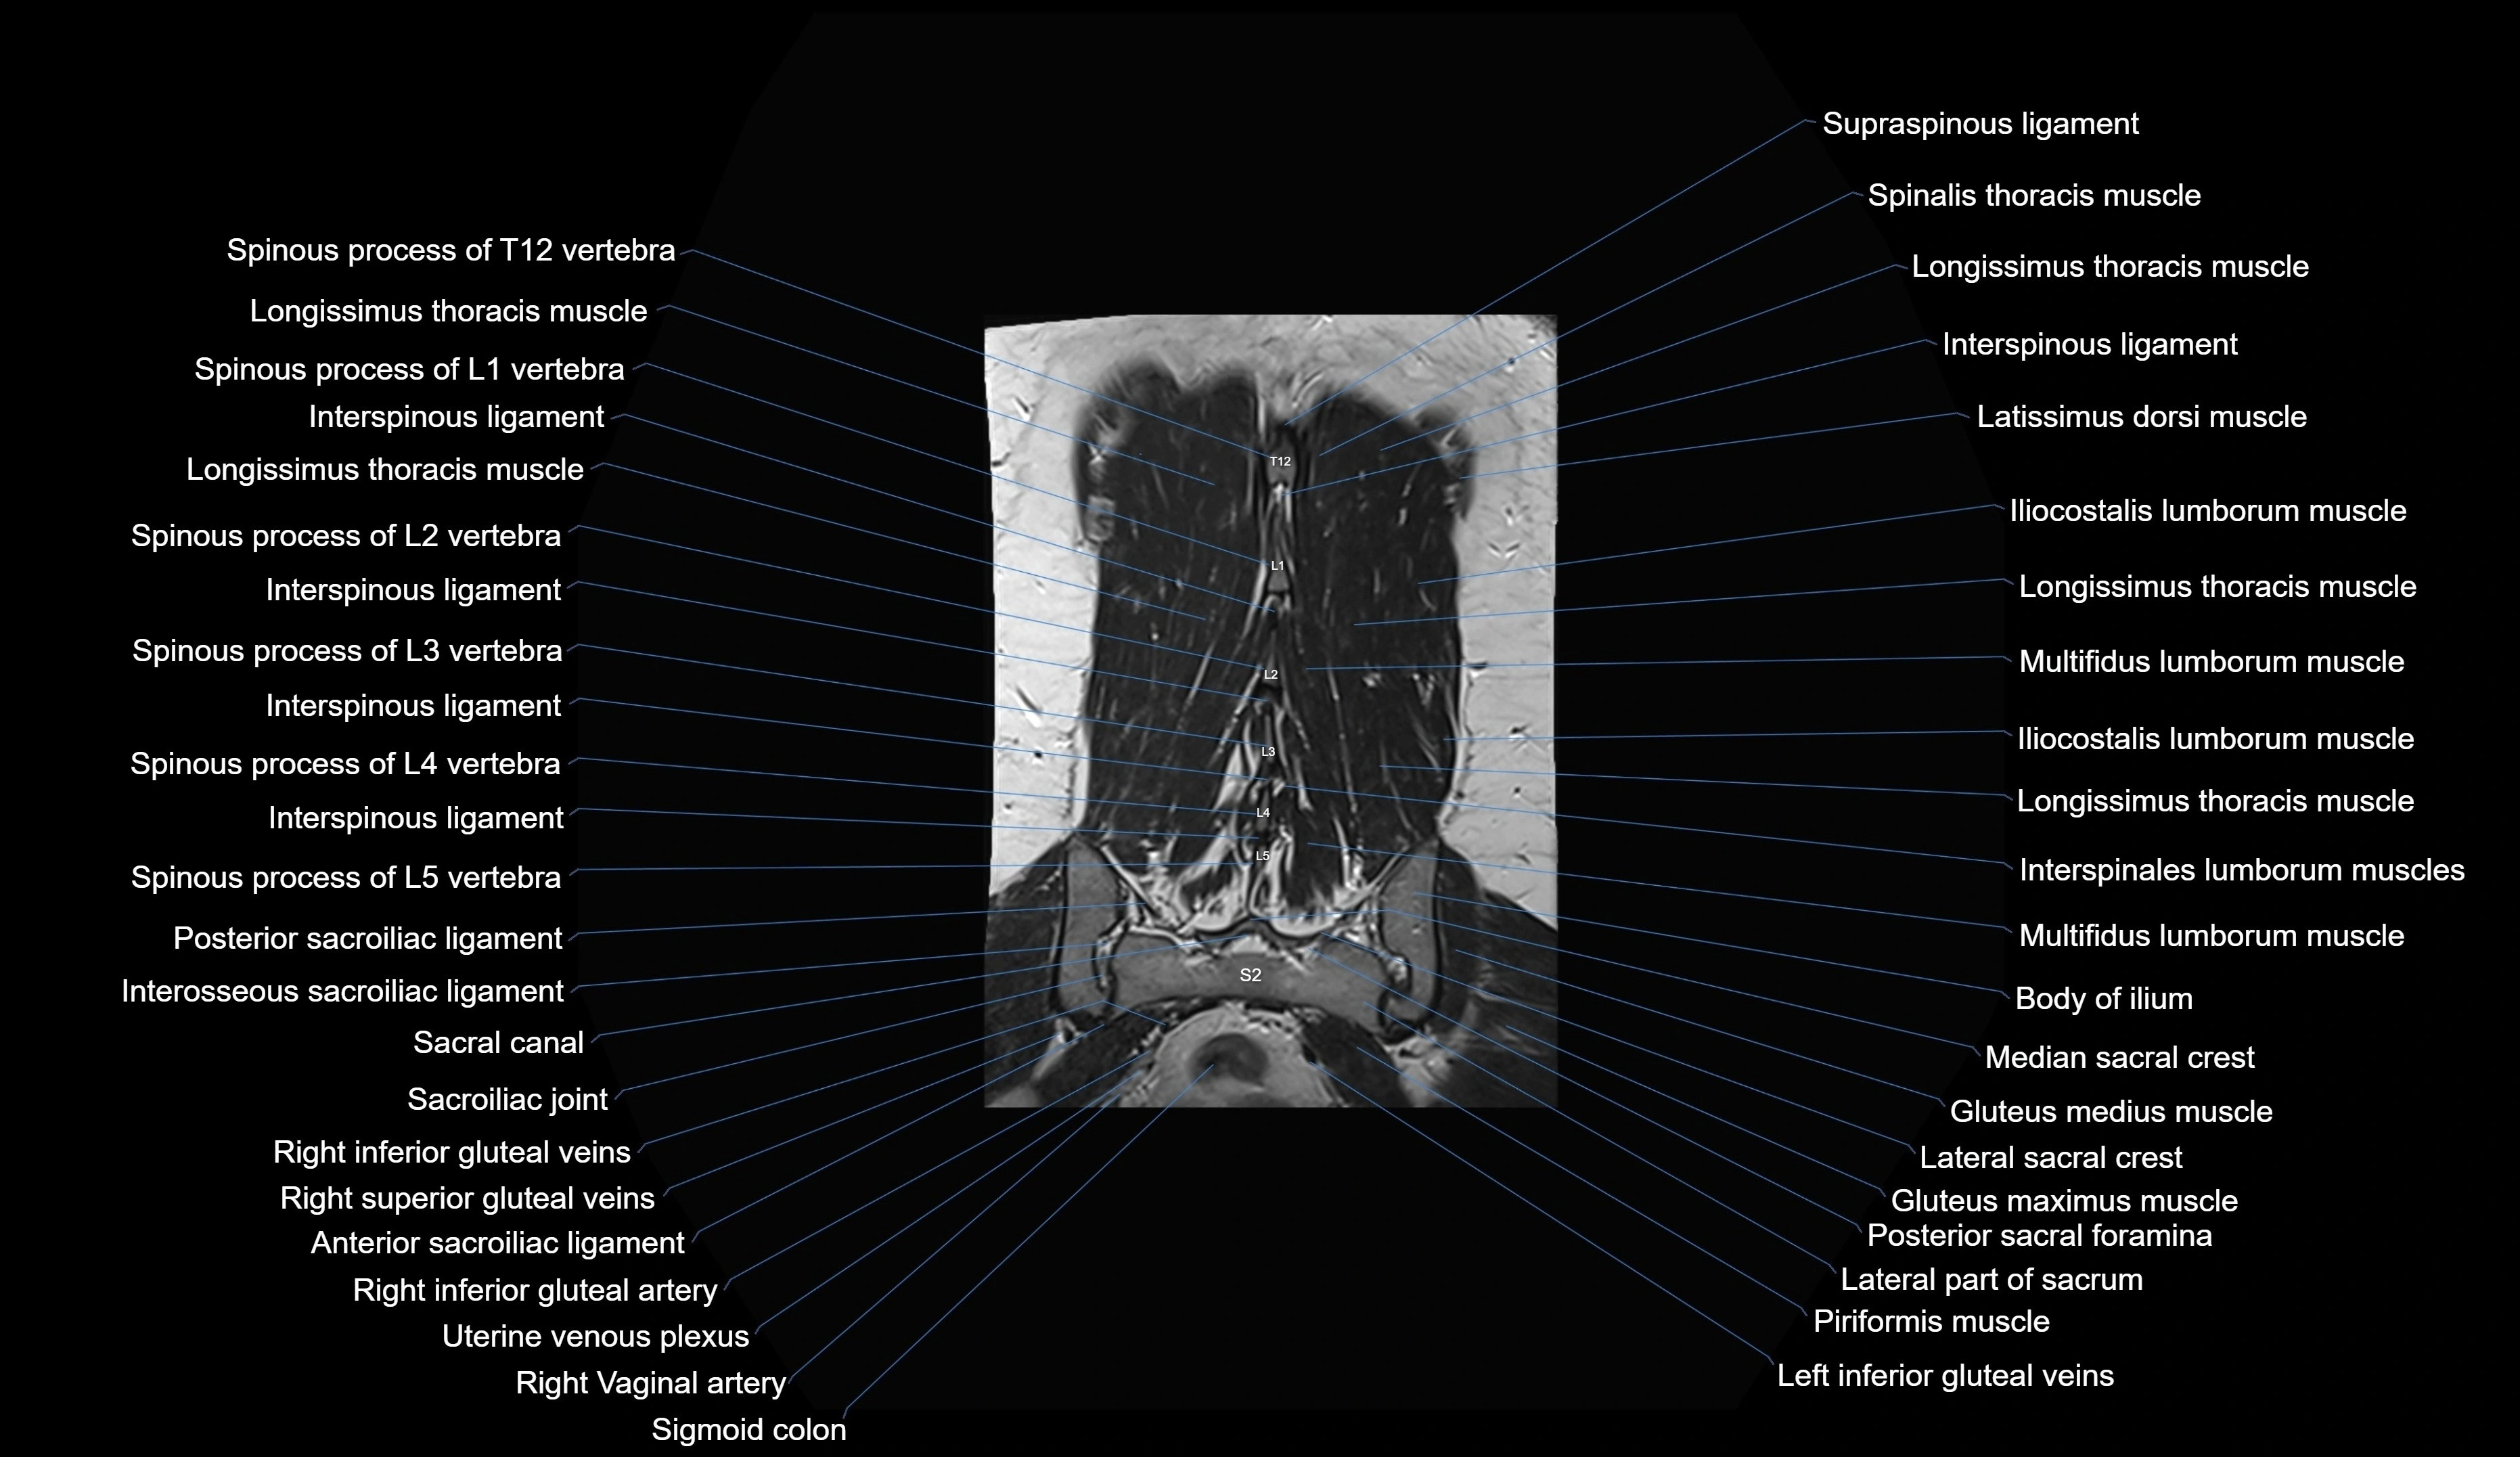

MRI images